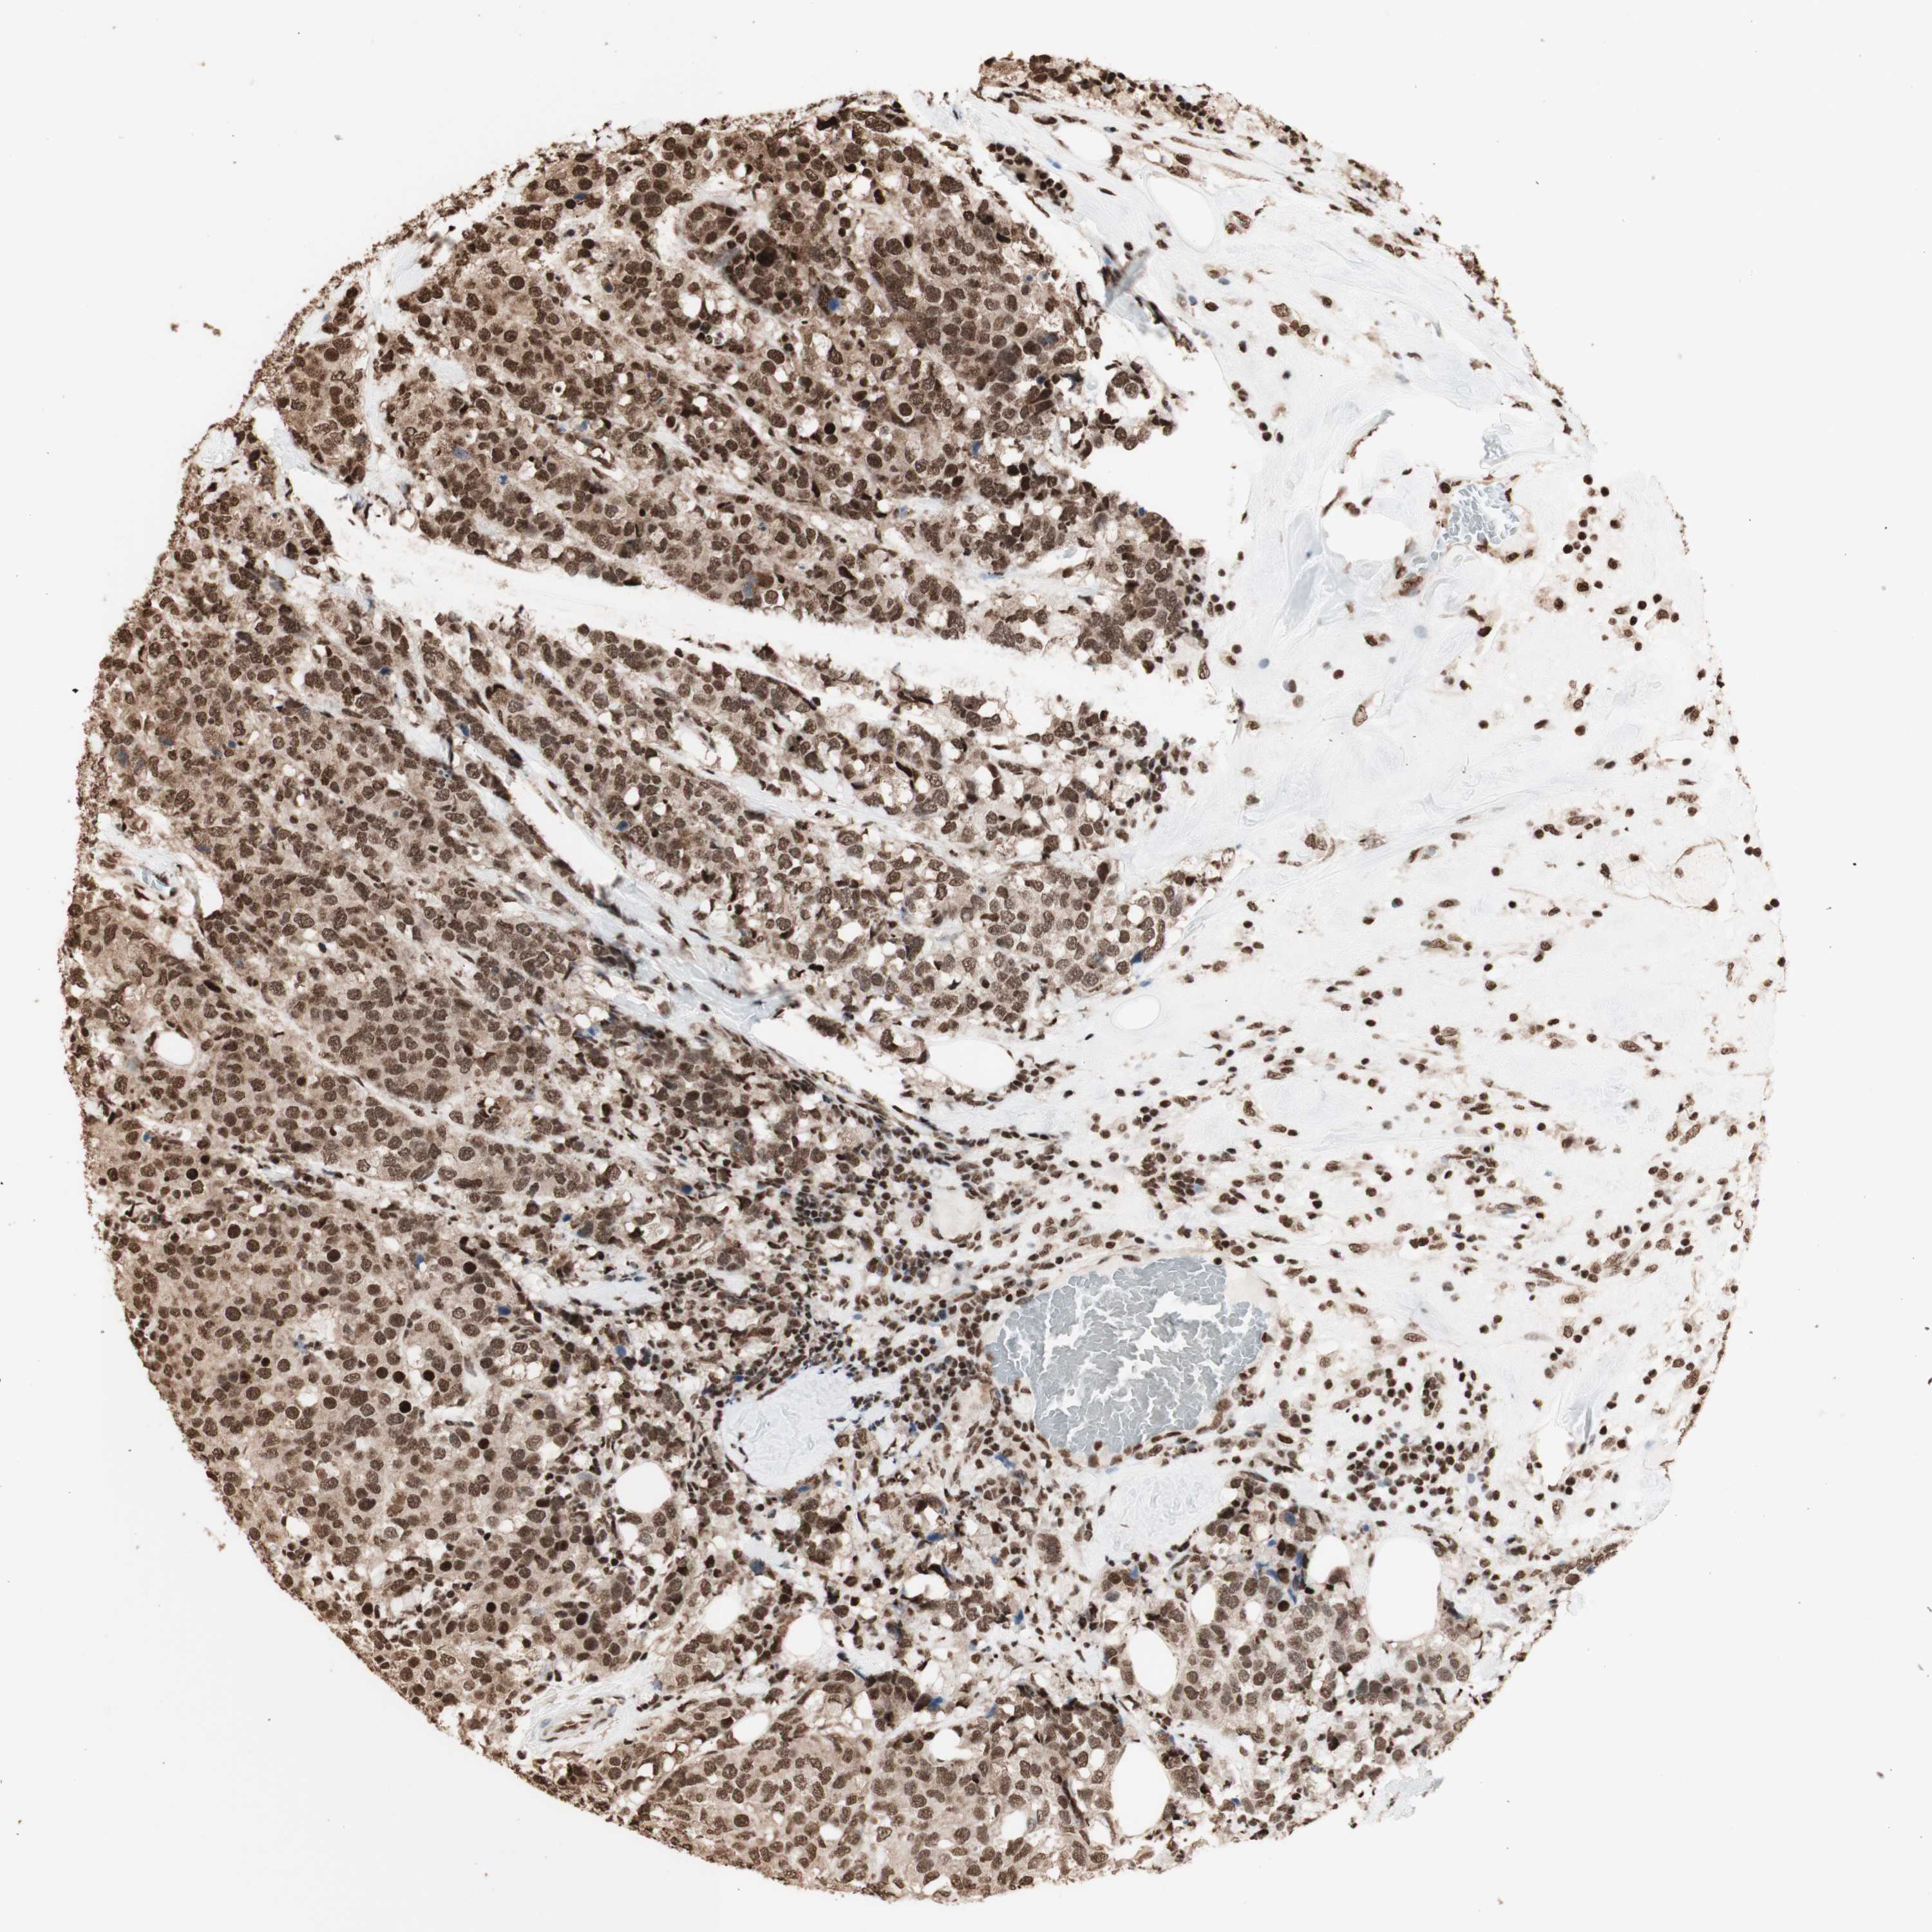

BRCA TCGA BRCA VALIDATION PROTEIN EXPRESSION

ANTIBODIES

AND

VALIDATION